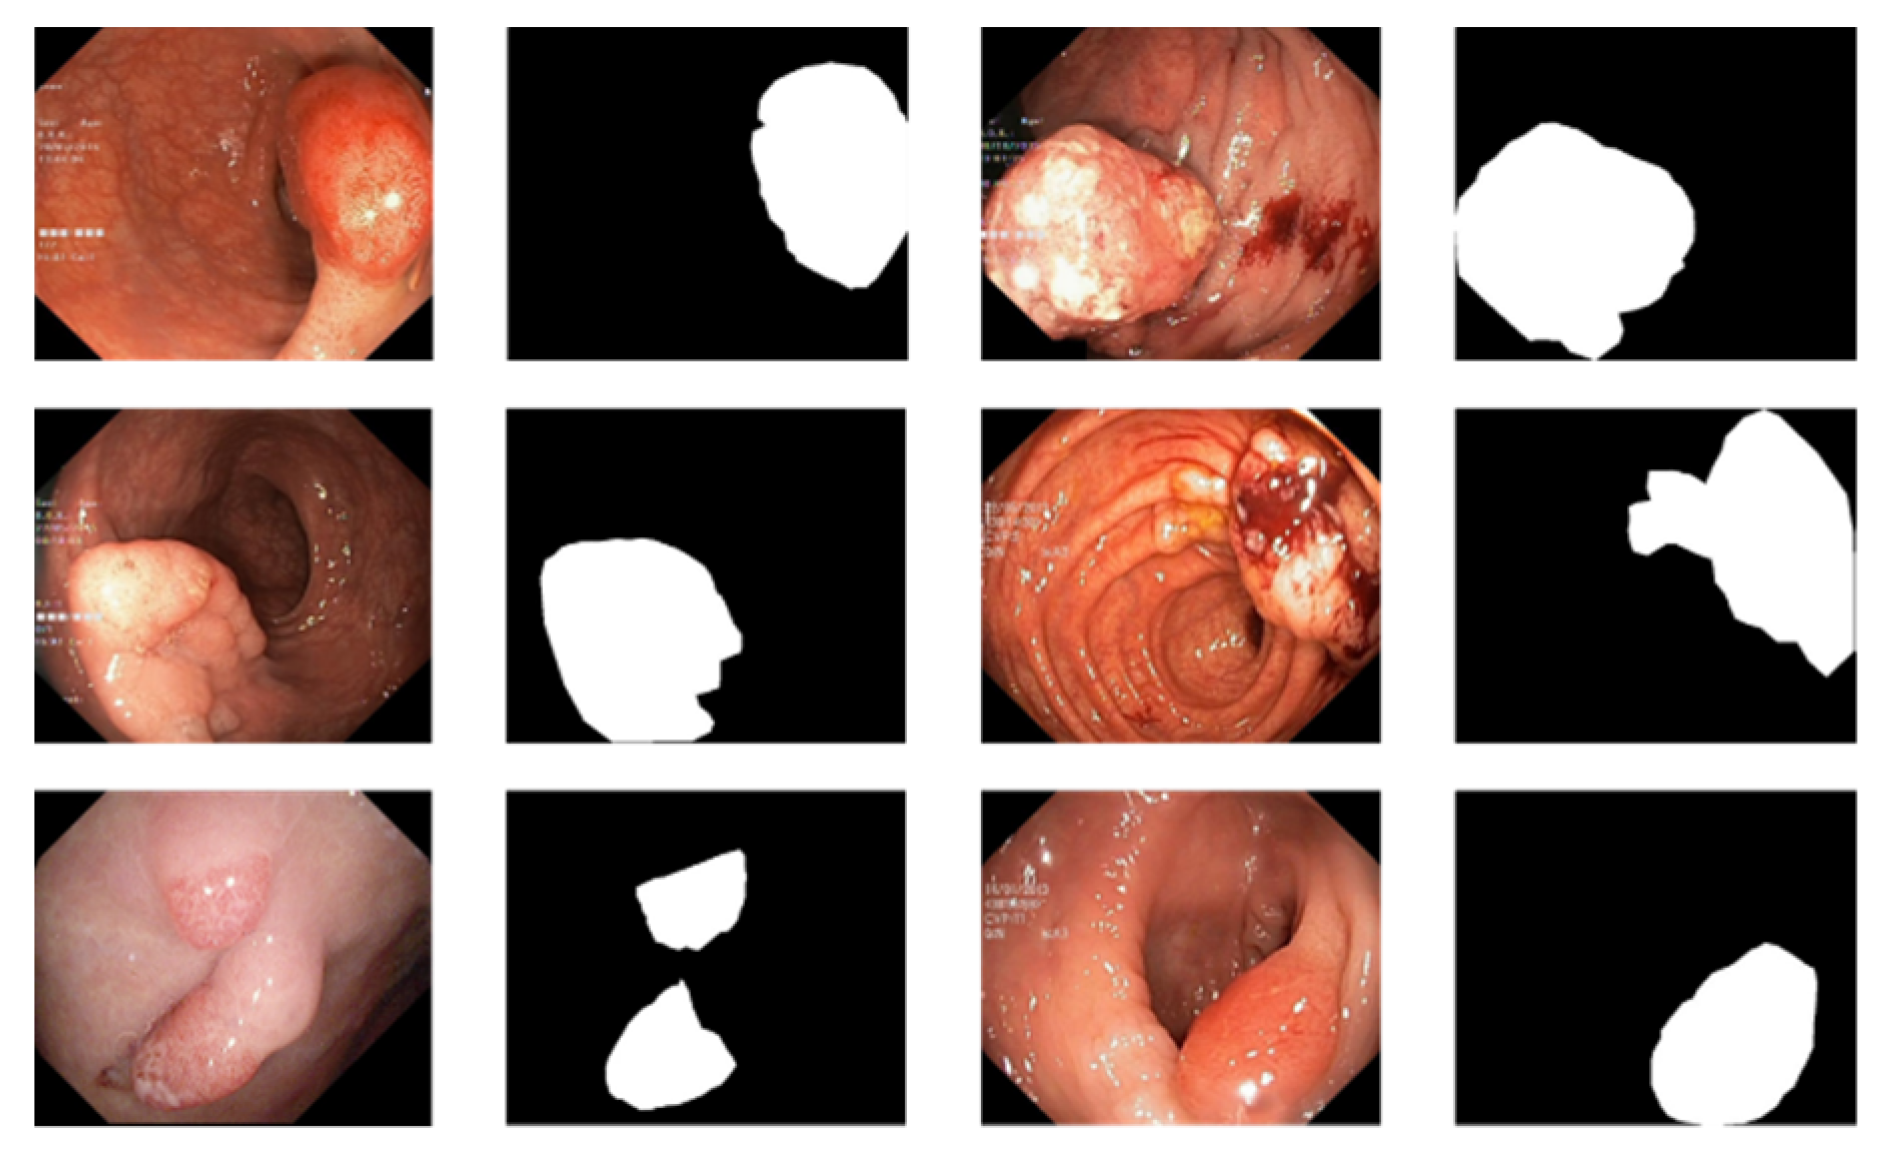

3.1. Data Preprocessing